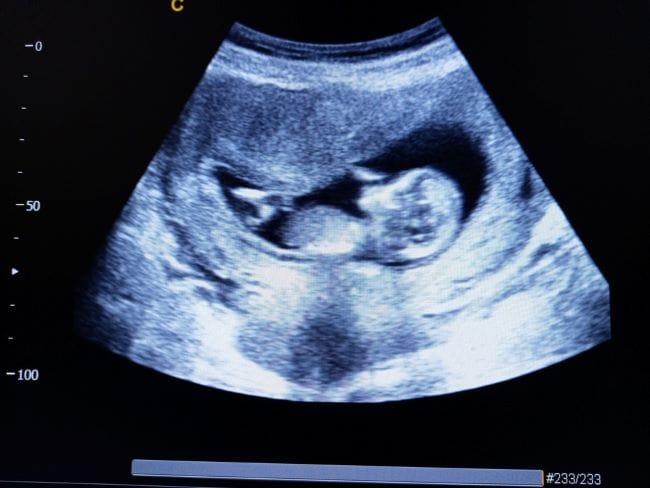

Pemeriksaan USG pada usia ini penting untuk memantau kesehatan organ vital janin, posisi plasenta, dan jumlah cairan ketuban. Jika terdapat hal yang tidak sesuai, pencegahan atau penanganan bisa dilakukan lebih cepat demi kesehatan Ibu dan Si Kecil. Tak jarang, USG pada usia ini juga bisa menunjukkan bentuk Si Kecil di dalam perut, serta gerakan kecilnya.

Pada hasil USG janin usia 14 minggu, dokter biasanya akan mengamati beberapa hal berikut sebagai tanda tumbuh kembang janin yang sehat:

Pada usia 14 minggu, panjang janin umumnya berkisar antara 8–10 cm dari kepala hingga bokong, dengan berat kurang lebih 40–50 gram. Melalui pengukuran ini, dokter bisa mengetahui apakah pertumbuhan janin sesuai usia kehamilan.

2. Bentuk dan gerakan tubuh janin

Di layar USG, bentuk tubuh janin mulai tampak makin jelas. Wajah janin sudah memperlihatkan ciri-ciri manusia, seperti letak mata, hidung, serta mulut yang mulai terbentuk.

Tangan, kaki, dan jari-jarinya pun terlihat, bahkan terkadang janin tampak melakukan gerakan sederhana, seperti menggenggam tangan, menendang, atau memutar tubuh. Meski Bumil belum bisa merasakan langsung gerakan ini, melihatnya di hasil USG janin 14 minggu sering menjadi pengalaman yang emosional.

3. Detak jantung dan perkembangan organ

Detak jantung janin di usia ini sudah kuat dan mudah dideteksi melalui USG, yaitu sekitar 120–160 kali per menit. Selain mendengarkan detak jantung, dokter juga memantau perkembangan organ utama, seperti otak, jantung, ginjal, hati, dan paru-paru.